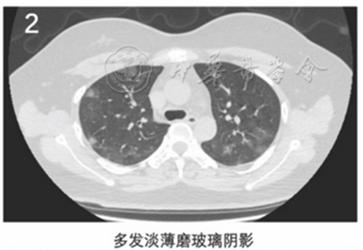

作者指出,2019新型冠状病毒肺炎有以下6个典型的CT影像学征像(图1~6):

(2)多发外周带磨玻璃阴影;